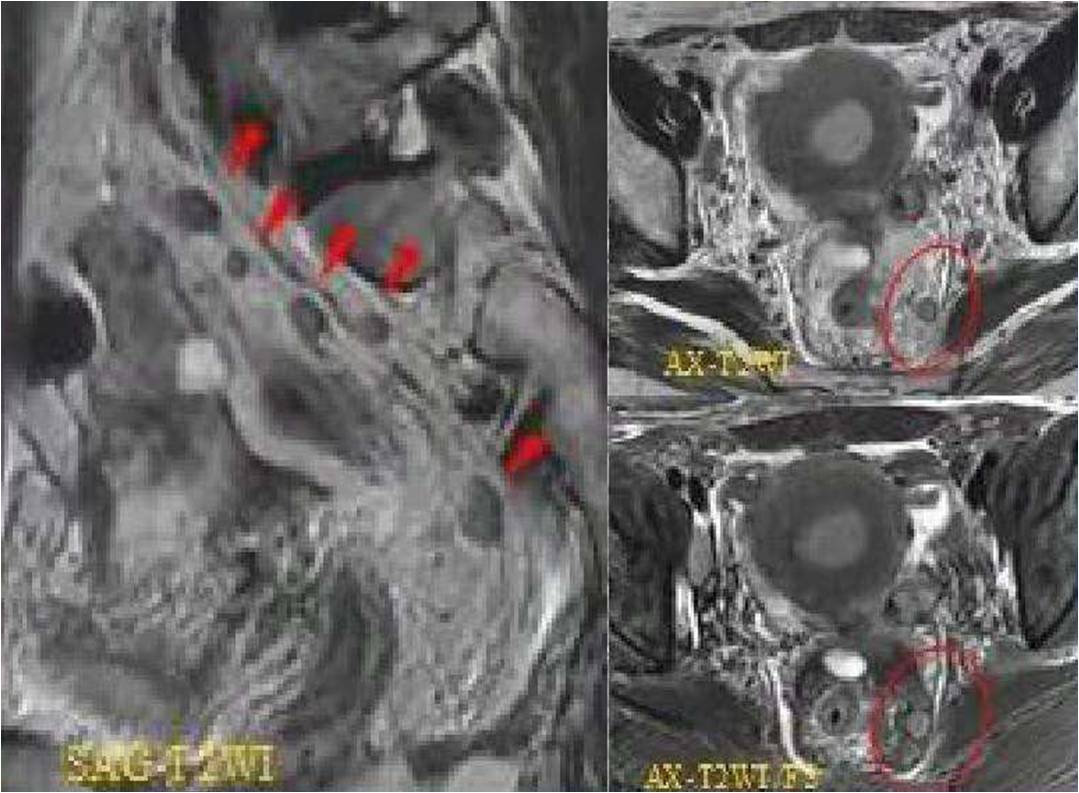

FIGO分期---子宮內膜癌

IA期 IB期 II期

III期 IV期

(三)子宮內膜癌分期思考

1. 宮頸是否受累影像判斷是難點(Ⅰ期還是Ⅱ期);